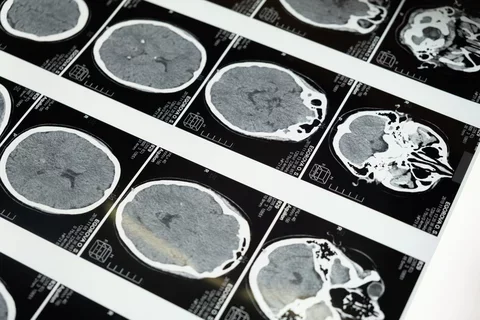

The Celebration of Día de los Muertos across the nation serves not only as a tribute to the departed but also as an opportunity for the Equity for Latinx/Hispanic Healthy Aging (ELHA) Lab at UCLA to initiate conversations about brain health. Latinos are 1.5 times more likely to develop Alzheimer’s disease than their white counterparts, but make up a small fraction of participants in the research. Founder of the ELHA Lab, Mirella Díaz-Santos (UCLA, RCMAR, CHIME ALUMNA 2019-20) is leading an effort to co-create and build partnerships with community-based organizations.